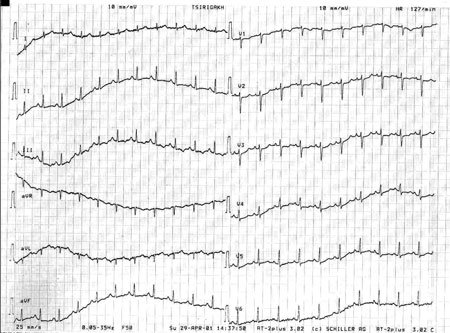

Εικόνα 3

Εικόνα 3. Ακτινογραφία θώρακος μετά την τοποθέτηση της θωρακικής παροχέτευσης.

Αμέσως τέθηκε η υποψία του δεξιού πνευμοθώρακα και πραγματοποιήθηκε ακτινογραφία σε ημικαθιστή θέση, με το φορητό ακτινολογικό μηχάνημα (εικόνα 2). Η τελευταία επιβεβαίωσε την υποψία και αποκάλυψε δεξιό πνευμοθώρακα, ο οποίος όμως δεν παρεκτόπιζε τις δομές προς την αντίθετη πλευρά (απουσία πνευμοθώρακα υπό τάση). Αμέσως η έγκυος οδηγήθηκε στο χειρουργείο, όπου και τοποθετήθηκε παροχέτευση (από ειδικό θωρακοχειρουργό) στο πάσχον ημιθωράκιο υπό τοπική αναισθησία και καρδιοτοκογραφικό έλεγχο του εμβρύου. Κατά την τοποθέτηση της παροχέτευσης διαπιστώθηκε έξοδος αέρα, αποδεικνύοντας έτσι την παρουσία του πνευμοθώρακα (εικόνα 3). Λίγα λεπτά μετά την τοποθέτηση της παροχέτευσης η κλινική εικόνα της εγκύου βελτιώθηκε σημαντικά, με υποχώρηση σχεδόν όλων των συμπτωμάτων. Παρέμεινε μόνο ένα μικρό άλγος στο ημιθωράκιο, το οποίο όμως ήταν καλά ανεκτό από την ασθενή.

Μετά από δύο ημέρες αποφασίστηκε η αφαίρεση της θωρακικής παροχέτευσης από τον ειδικό θωρακοχειρουργό. Όμως, κατά τον κλινικό και ακτινολογικό έλεγχο της επομένης ημέρας εμφανίστηκε υποτροπή του πνευμοθώρακα και έτσι επανατοποθετήθηκε η θωρακική παροχέτευση. Μετά από δύο ημέρες επιχειρήθηκε εκ νέου η αφαίρεση της παροχέτευσης, η οποία όμως δεν ήταν εφικτή, γιατί ο πνευμοθώρακας υποτροπίασε. Στον καρδιολογικό έλεγχο (με τη θωρακική παροχέτευση σε λειτουργία) το ΗΚΓ παρουσίαζε σαφή μεταβολή: ΚΣ=60/λεπτό, τα αρνητικά «Τ» δεν υπήρχαν, ενώ τα επάρματα «R» στις απαγωγές ΙΙΙ και V5 είχαν μικρύνει (εικόνα 3), στοιχεία που είναι συμβατά με τη μείωση του πνευμοθώρακα σε σύγκριση με αυτόν της εισόδου.